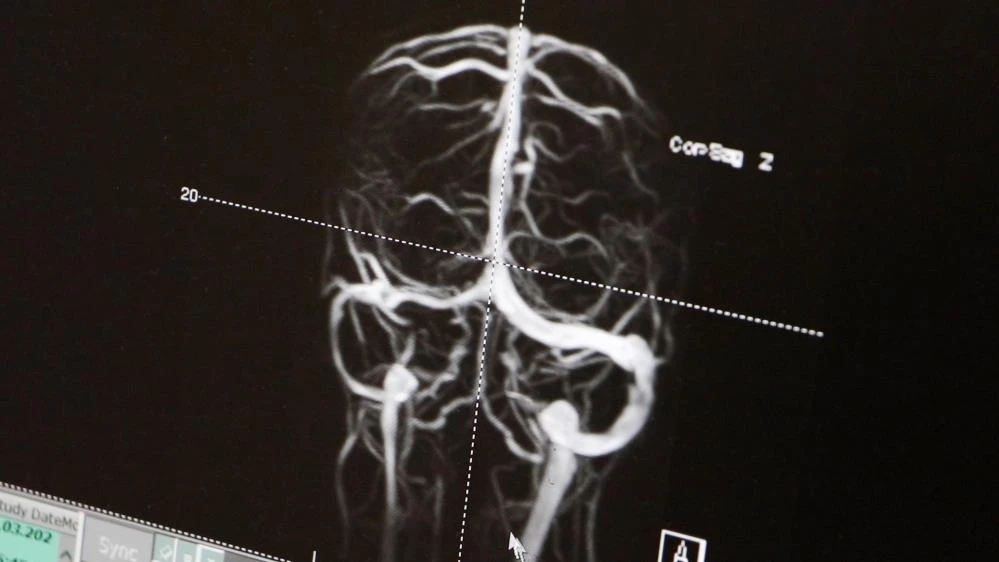

"MR venografi dediğimiz bir yöntemle, beynin toplar damarlarında kan akımında bir anormallik olup olmadığını araştırıyoruz. Uygun hastalarda, beyin omurilik sıvısının (BOS) basıncını ölçerek, yüksek olup olmadığını değerlendiriyoruz. Özellikle doğurganlık çağındaki obez kadınlarda sık görülen bu hastalığın çocuklarda da çok sık olduğu bilinmektedir. Son 5 yıllık meslek hayatımda 45 tane olguya tanı ve tedavi uyguladım."

"Buradaki en büyük avantajımız, geniş etiyolojik testleri tüm hastalarımıza uygulayarak altta yatan nedeni ortaya koymamız oldu. Hastamız Elisa özelinde düşünürsek, bu etiyolojik testler sonucunda hastamızın beyin toplar damalarında bir pıhtı olduğunu gördük. Genetik olarak da pıhtı oluşumuna yol açan bir faktörün hem anneden hem babadan Elisa’ya aktarıldığını saptadık. Çocuk Hematoloji departmanımızla birlikte önce trombolitik, sonra da antitrombotik koruyucu tedavi ile hem kafa içinde artmış basıncı düzelttik, hem de pıhtıyı erittik" diye konuştu.